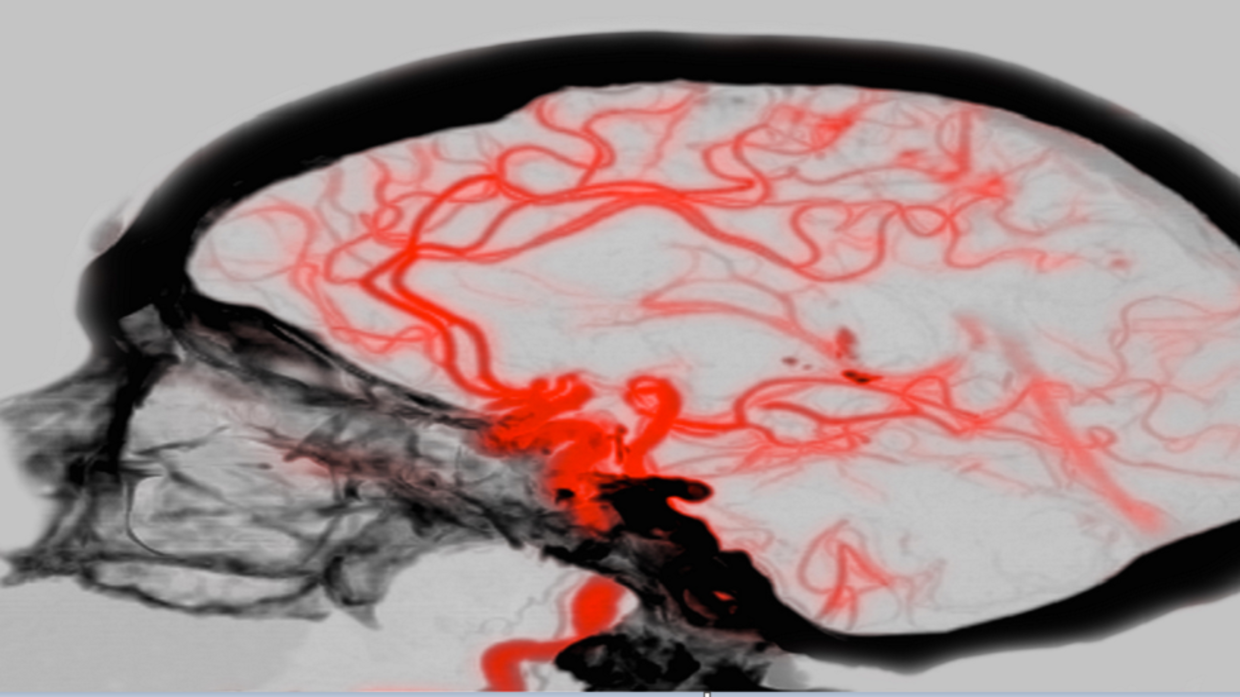

An international consortium of researchers, led by the University Health Network (UHN) in Toronto and the University of Zurich, has created the first molecular atlas of the human brain's vasculature with unprecedented resolution.

This advanced atlas reflects several stages, from early development to adulthood as well as disease stages, such as brain tumors and cerebrovascular malformations.

In the study, the researchers isolated blood vessels from early developing human brains, adult brains, brain tumors, and brain vascular malformations.